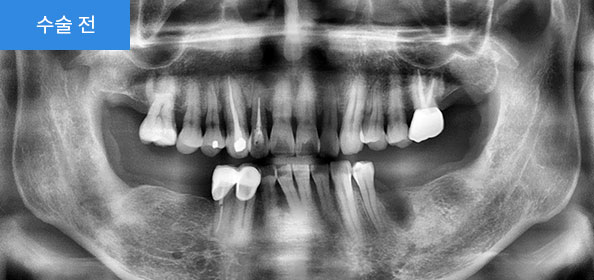

2020.06

아랫부분에 틀니를 사용하시다가 불편하셔서 방문하셨습니다.

2021.04

치아가 없는 아랫부분에 네비게이션(가이드)임플란트로, 기존에 뺐다 꼈다 했던 불편한 틀니 대신 좀 더 음식을 잘 씹을 수 있는 임플란트로 진행하였습니다.